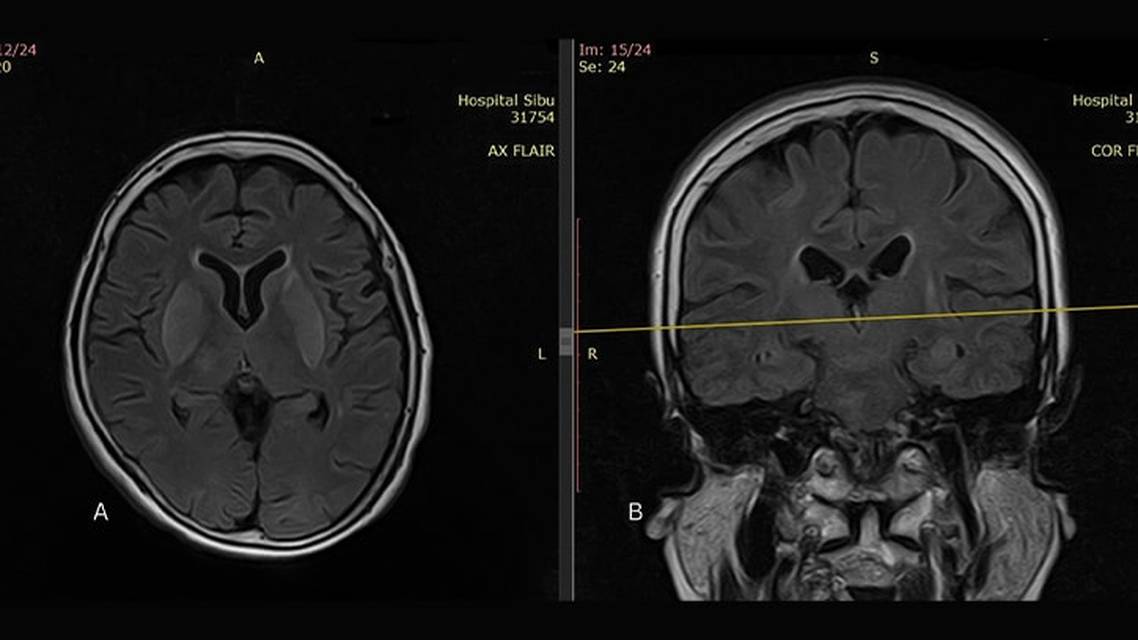

MRI showed abnormal hyperintensity signals at both lentiform nuclei, thalami, caudate nuclei, and hippocampus, as well as in pons, midbrain, and medulla oblongata on T2-weighted images (Figure 2). Restricted diffusion was noted on diffusion-weighted imaging and patchy enhancement was evident in the postcontrast study. There was also a long segment of intramedullary hyperintense signal on T2-weighted images from spinal level C3 to T3, predominantly affecting the anterior horn of the spinal cord (Figure 3).

Laothamatas et al6 described abnormal T2 hyperintensity signals in the brainstem, hippocampus, hypothalamus, deep and cortical gray matter, and gray matter of the spinal cord in their case series of individuals with rabies. MRI brain findings in our patients were similar to those reported in the available literature.5-8 There are characteristic abnormal signals in T2-weighted images involving deep grey nuclei and the brainstem.

Rabies is a life-threatening zoonotic infection that is nearly always fatal after clinical signs have developed. The diagnosis is secured by a compatible history of rabid animal bite with progressive rhomboencephalitis, ultimately leading to death. The predilection of gray matter and brainstem to show abnormal hyperintense signal on T2-weighted images in an MRI of the brain can raise the suspicion of rabies even before laboratory confirmation can be obtained as not all centers run these tests. Hence, every person with high-risk exposure should receive proper wound management that includes adequate wound washing with running water and soap followed by RIG and vaccination. PEP is important after bites from a rabid animal have occurred. PEP needs to be administered with strict adherence to protocol; failure to follow protocol may result in clinical manifestation of human rabies. Wound debridement should be delayed for at least 6 hours after RIG infiltration for people who sustain multiple deep wounds.